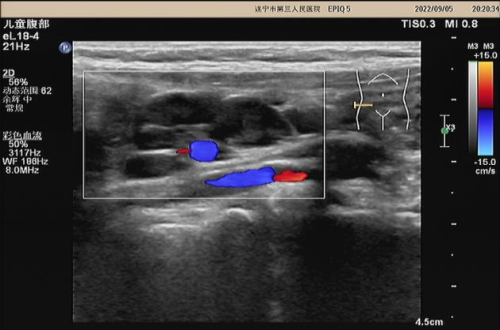

超声对小儿肠系膜淋巴结肿大的解读

秋冬季来啦,很多腹痛的宝宝,到了医院就会进行超声检查,其中不少会查出“肠系膜淋巴结肿大”,小儿肠系膜淋巴结肿大在儿科门诊中发生率极高,其原因有生理性和病理性之分...